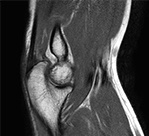

Пример МРТ локтевого сустава

МР-томография локтевого сустава

Соотношение костей в суставе правильное. Плечевая, лучевая и локтевая кости имеют типичную конфигурацию. Олекранон и короновидный отросток не изменены. В зонах надмыщелков плечевой кости, бугристостях лучевой и локтевой костей отека костного мозга не выявлено.

Контуры костей незначительно деформированы за счет краевых остеофитов.

Суставные поверхности, субхондральные отделы с явлениями остеосклероза.

Суставная щель незначительно сужена, суставной хрящ неоднородный, умеренно истончен.

В плечевой кости выявляются мелкие субкортикальные кисты размерами до 2-4мм.

Определяется изменение сигнала и разволокнение общего сухожилия разгибателей кисти.

Остальные мышцы и сухожилия имеют правильную конфигурацию, типичный ход, неизмененную структуру.

Мягкие ткани локтевой области без особенностей.

Визуализируется небольшое количество жидкости в полости сустава.

ЗАКЛЮЧЕНИЕ по снимку МРТ локтевого сустава: МР-картина артроза локтевого сустава 2ст. Небольшой суставной выпот. Тендинопатия общего сухожилия разгибателей кисти.